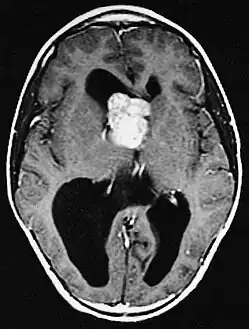

MRI of brain with sub-ependymal giant cell astrocytoma

Diagnosis is made by imaging with a contrast-enhanced MRI or CT scan of the brain.[3]